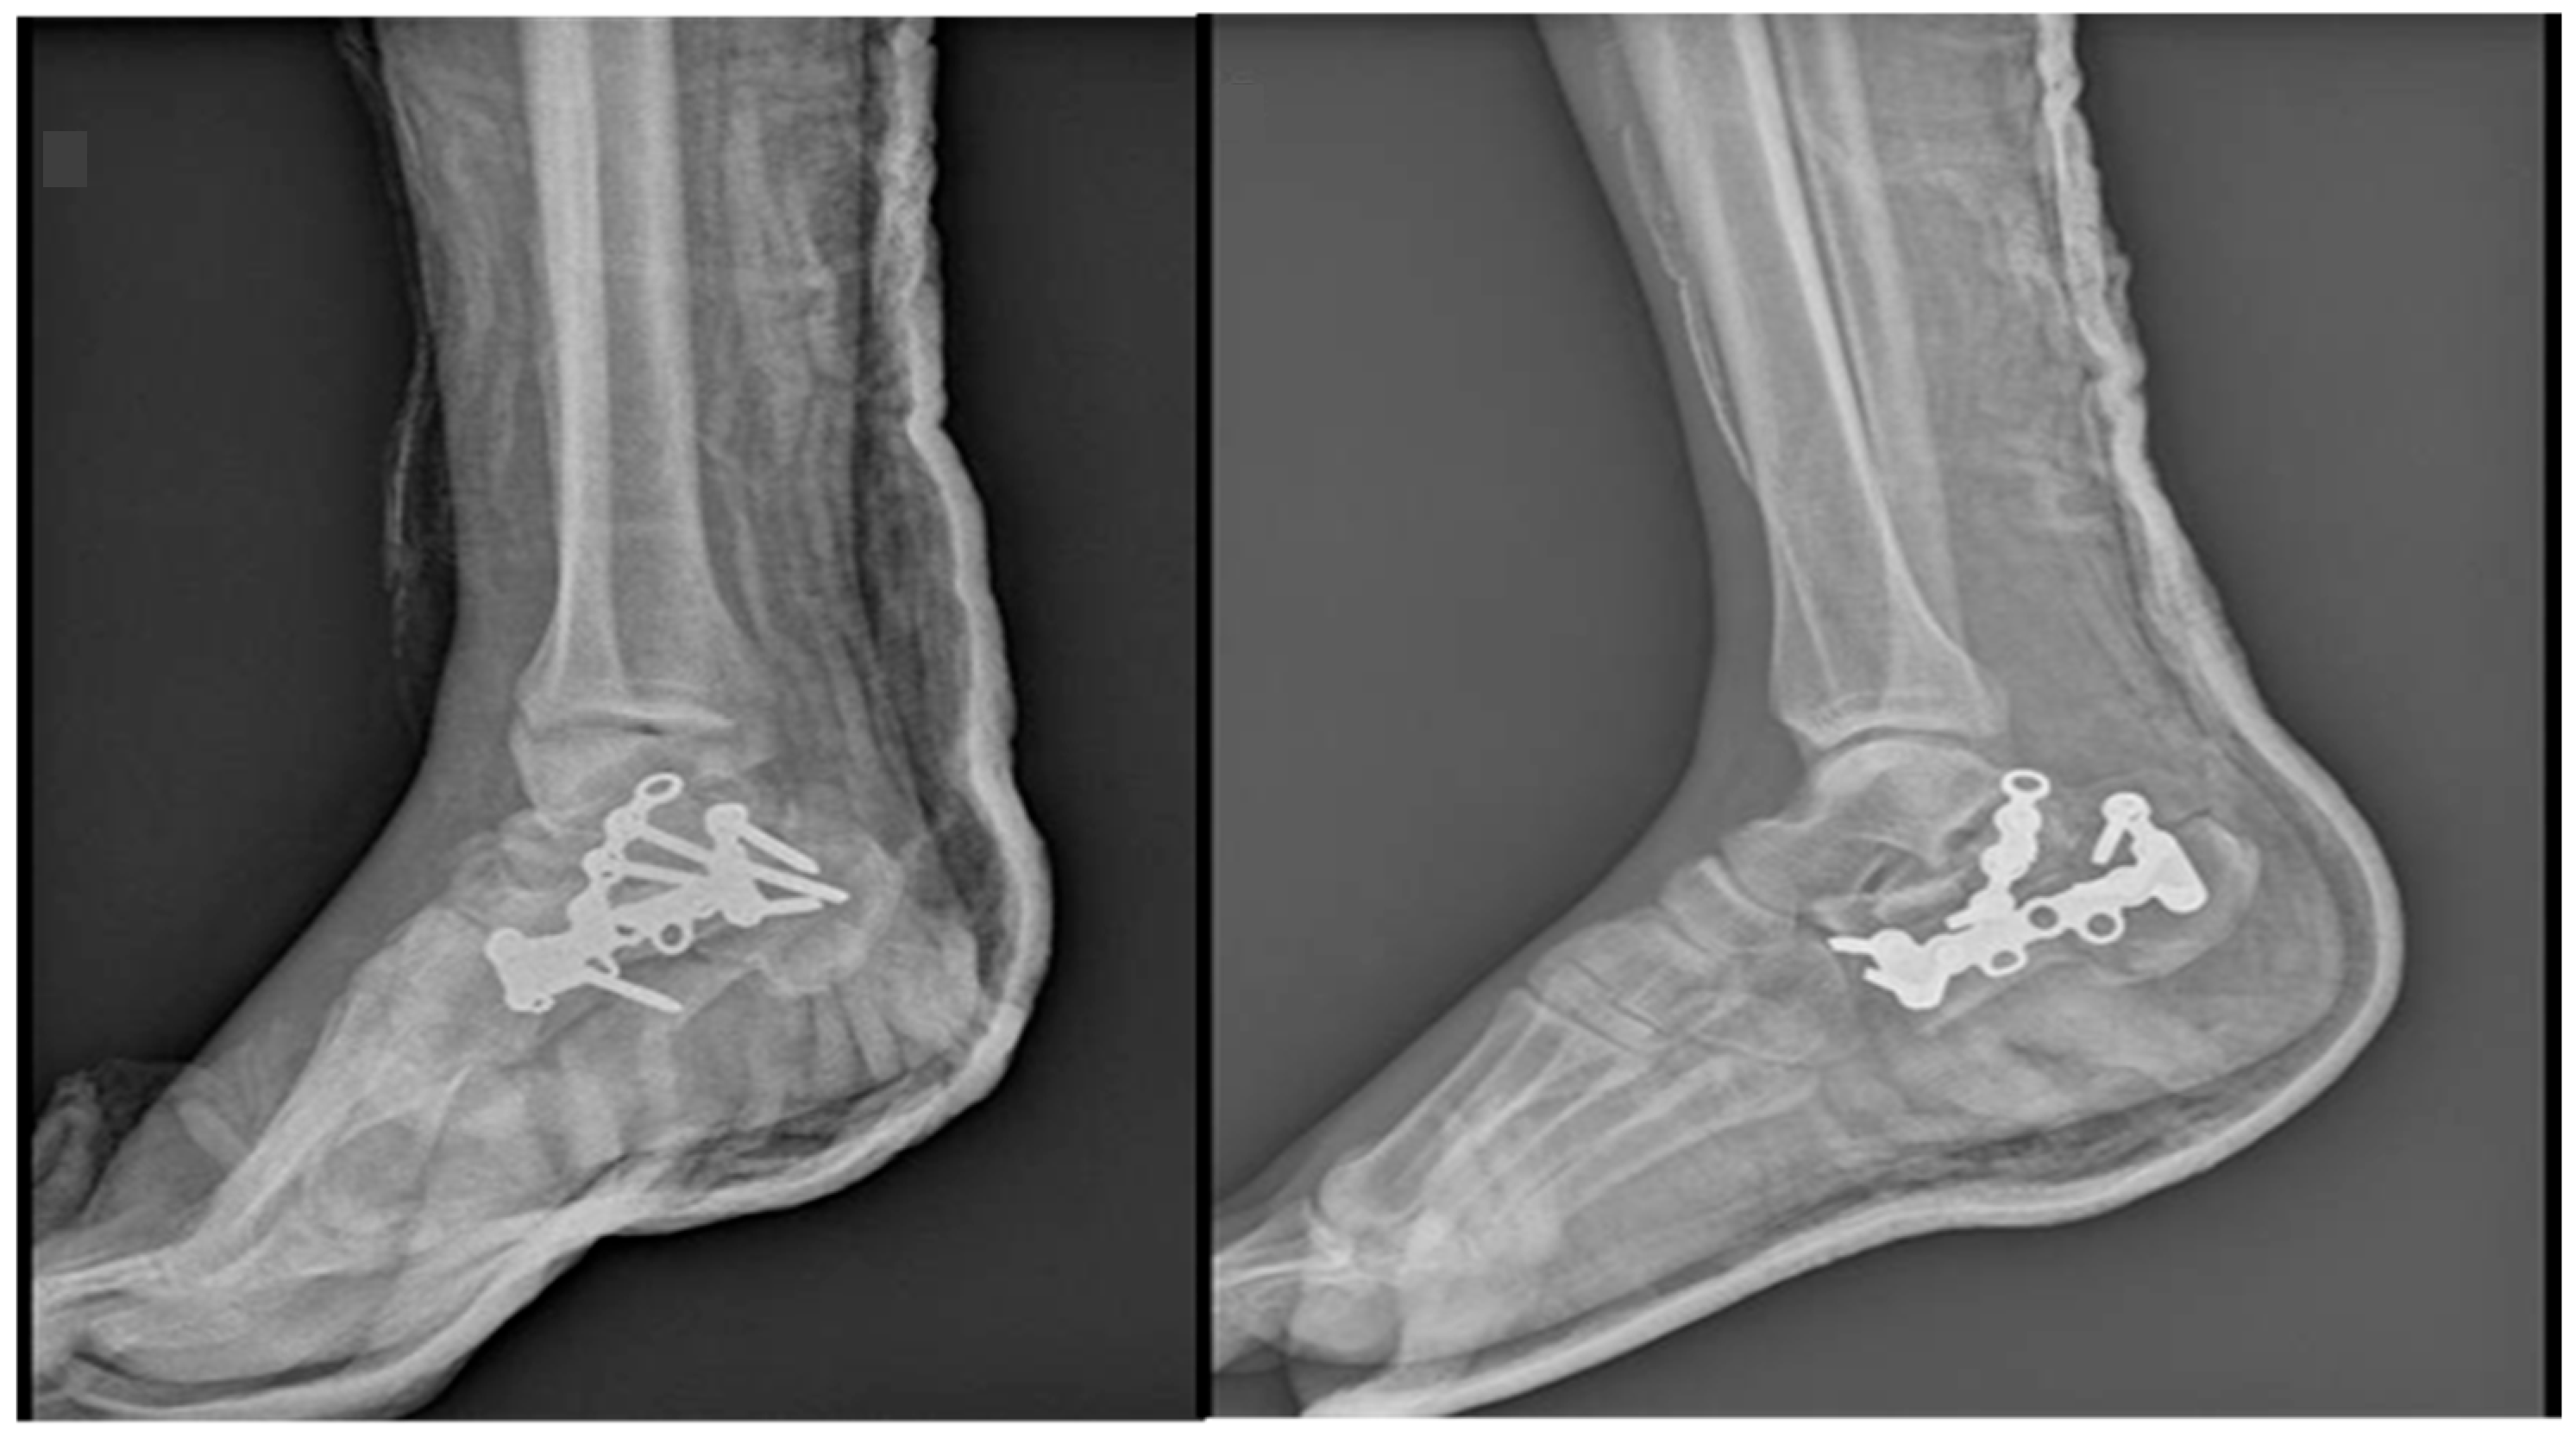

Figure 3. X-rays after ORIF of the right calcaneus fracture.

Local evolution was good, the edema diminished, and the conditions improved so that the patient was suitable for surgery. The right calcaneal fracture has been treated by ORIF with a calcaneal plate and screws and an additional autogenous bone graft harvested from the level of the right iliac crest through a lateral approach. Figure 3. For the left calcaneal fracture, the treatment has been non-surgical using immobilization with non-weight bearing for 6–8 weeks. The patient is discharged because of the early good local and general evolution.